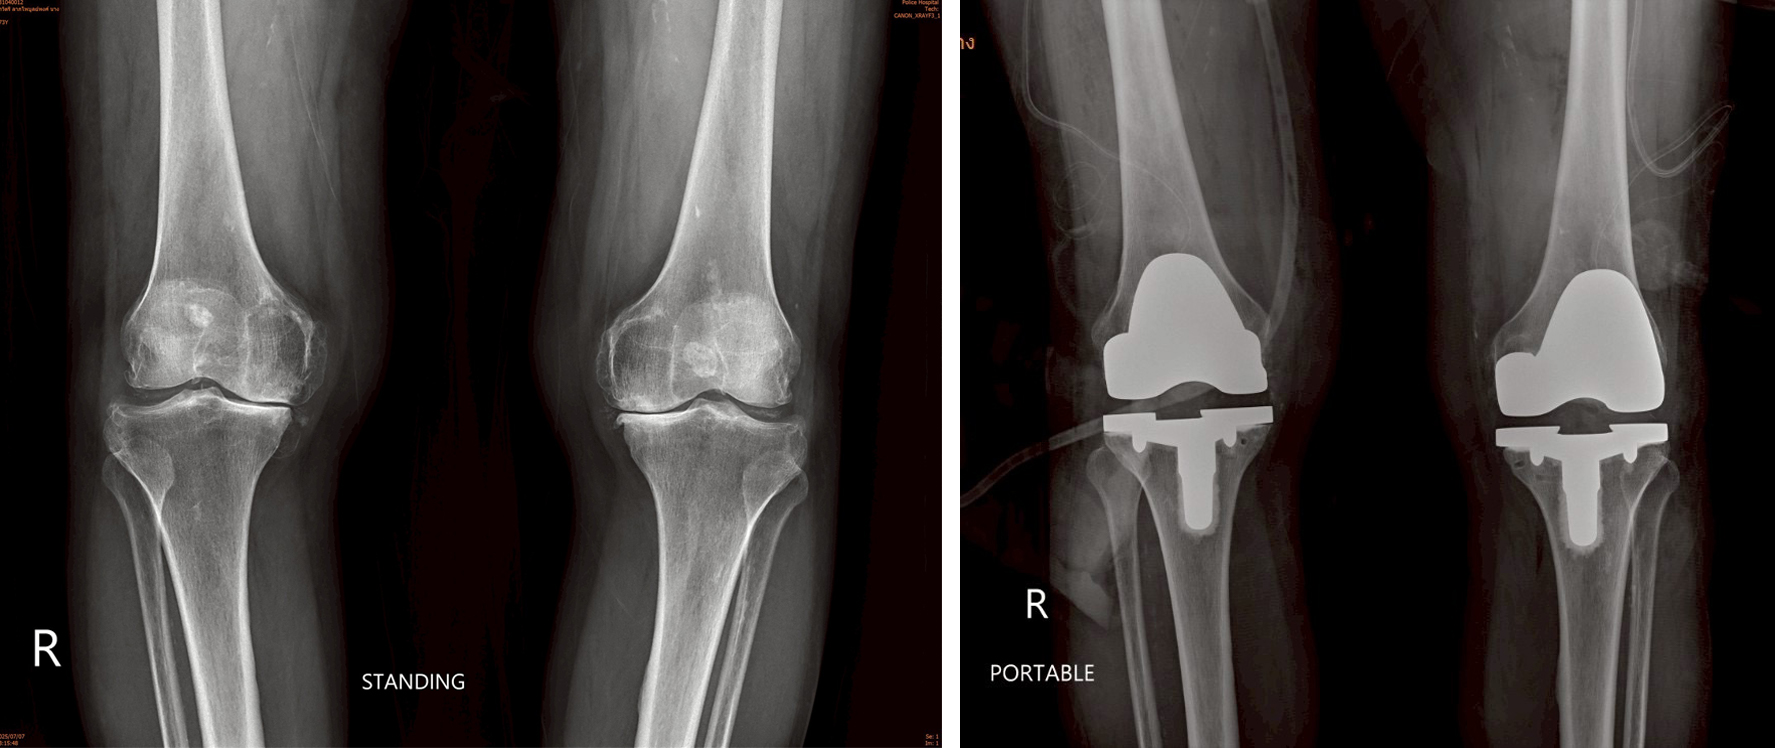

ผ่าตัดเปลี่ยนข้อเข่าเทียม ด้วยเทคนิค “ไม่ตัดกล้ามเนื้อ” (Muscle Sparing)

การผ่าตัดเปลี่ยนข้อเข่าเทียมด้วยเทคนิควิธี “ไม่ตัดกล้ามเนื้อ” (Muscle Sparing)เป็นวิธีที่ลดอาการปวดหลังผ่าตัด และสามารถฟื้นตัวได้อย่างรวดเร็ว  สามารถผ่าตัดได้ทั้งทีละข้าง  หรือพร้อมกันทั้ง 2 ข้างได้